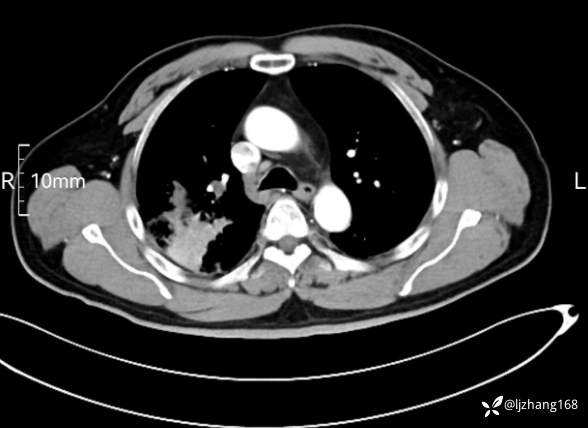

中年男患,右肺团片影,炎症0R肿瘤?

辅助检查:糖化血红蛋白12.3%。肺炎支原体IgG、IgM、呼吸道合胞病毒均未见明显异常。胸部CT:右肺上叶阻塞性肺炎。

讨论:诊断及鉴别